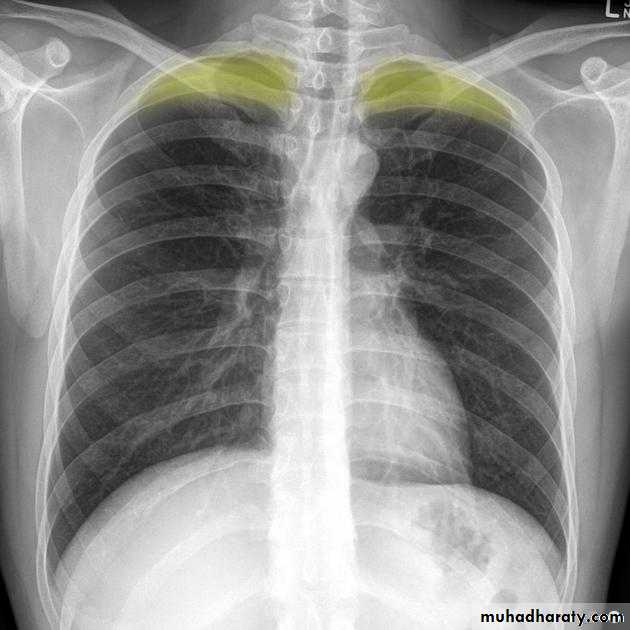

Blunting of CP angle